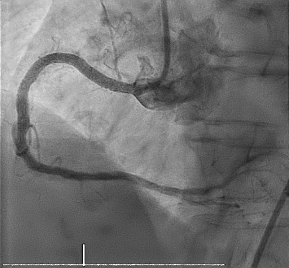

支架植入术后